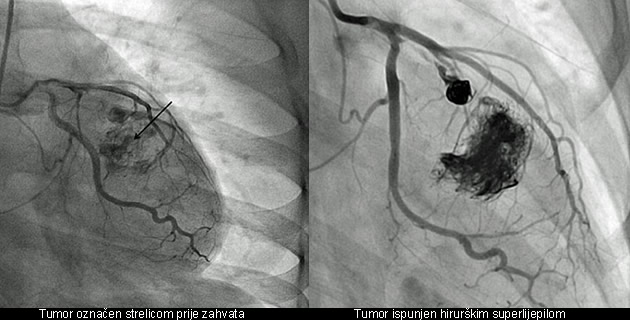

Liječnici su joj objasnili kako se rodila s tumorom, ali je nastavio rasti i izvan srca. Pokušali su joj ga izvaditi, ali nakon što su je otvorili na operacijskom stolu, vidjeli su da ne mogu ništa napraviti. Transplantacija srca, također, nije više bila opcija jer ne bi dobili srce na vrijeme. Dr. Cave razgovarao je s kolegom koji je napravio sličnu operaciju na mozgu. Došao je na ideju. Umetnuli su tanki kateter u srce i izlili četiri tube hirurškog superlijepila. Prije su već pokušali spriječiti dovod krvi u tumor, ali pronašao je novi izvor. Nevjerojatnu operaciju objavili su svi medicinski časopisi.